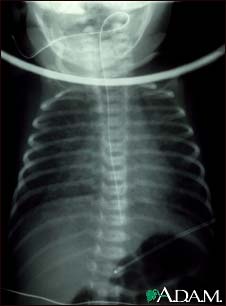

Totally anomalous pulmonary venous return (TAPVR) is a form of congenital heart disease. This x-ray shows an enlarged heart, a large liver, and increased size of the lung blood vessels (pulmonary vascularity).